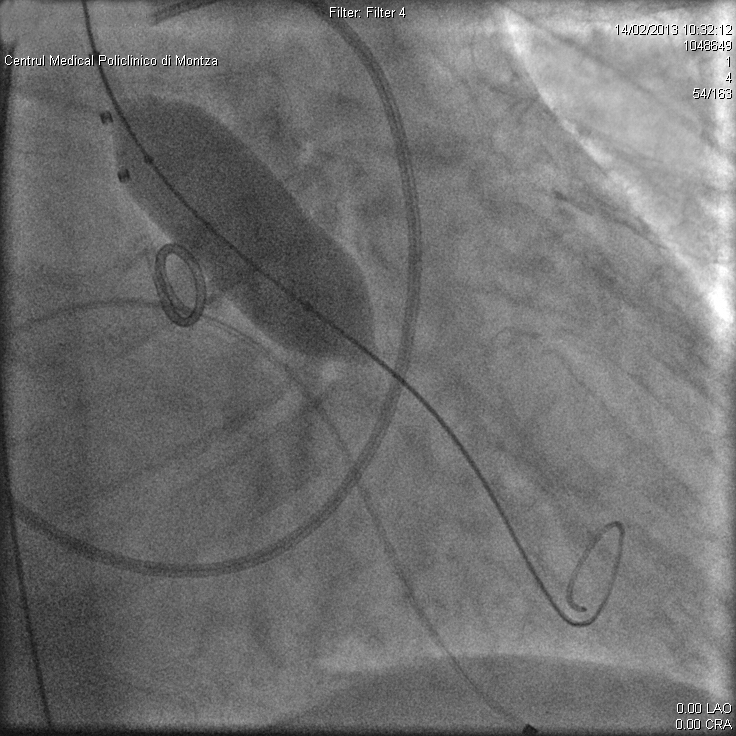

Astfel, s-a imaginat o procedură de implantare valvulară aortică transcateter (TAVI/TAVR) prin care în interiorul valvei îngustate a pacientului se introduce un balon de dimensiuni adecvate cu care valva îngustată este, mai întâi, dilatată sub control radiologic și ecografic transesofagian (fig. 2).

Imaginile prin care sunt ilustrate etapele de implantare a unei proteze valvulare aortice sunt preluate de la primul pacient, în vârstă de 62 de ani, care a depășit cu succes această procedură în Laboratorul de Cardiologie Intervenţională al Spitalului Monza, în luna februarie 2013.